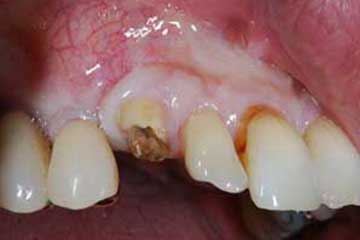

Impianto post-estrattivo

In un paziente cardiopatico di 72 anni